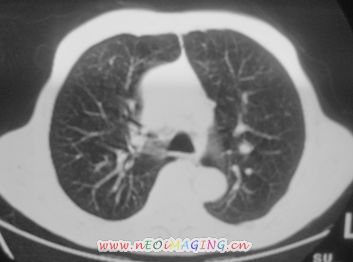

以下是引用卜一在2007-10-7 9:38:00的发言:[br]左下肺胸膜下团片影,内见含气支气管像,临近胸膜未见增厚。多考虑:1 左下肺炎症,建议消炎后复查!2 不除外肺隔离症合并感染!